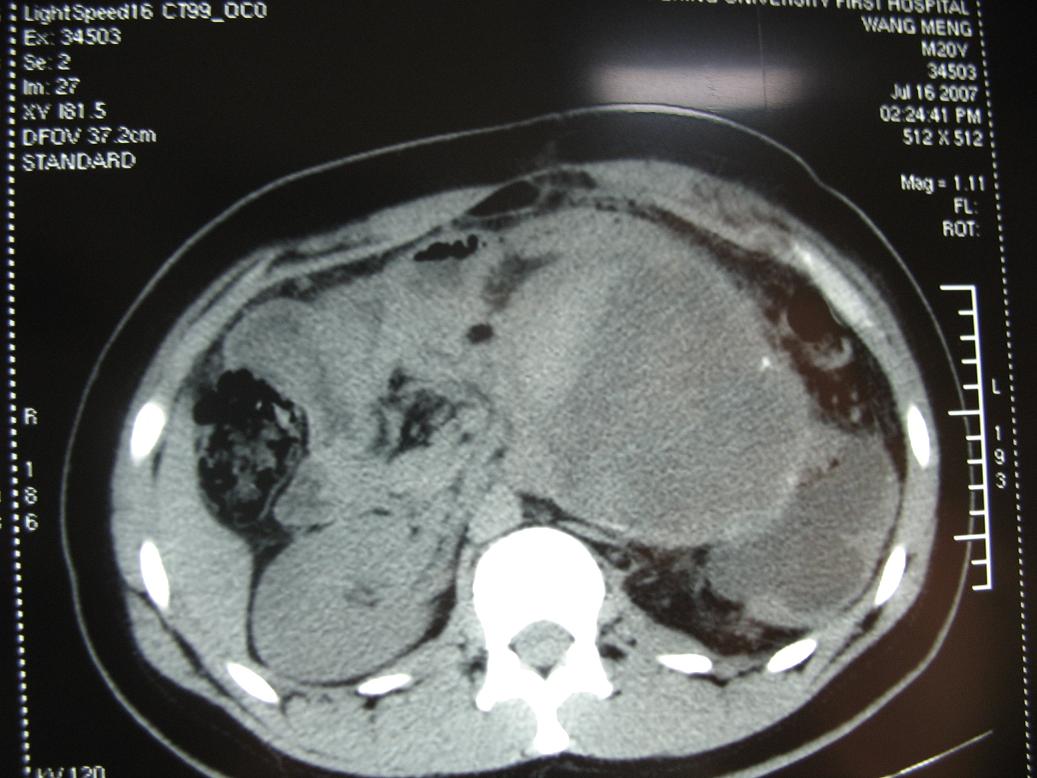

无肠梗阻及主动脉受压向前右移位,应该定位于腹膜后肿瘤,囊实性密度,内可见点状钙化影,及出血征象,患者年龄轻,考虑畸胎瘤或生殖细胸胞瘤可能性大.蒙一下.

考虑腹后肿瘤,肿瘤前缘与左腹直肌有条状影相连,且左腹直肌和相邻腹膜稍厚,腹主动脉有被包绕改变,提示恶变的可能。

定位肿瘤在腹膜后没问题,包膜完整与左肾门及腹主动脉关系密切。腹膜后未见明确异常增大淋巴结,左肾积水增大,但要考虑肠间质瘤就不是腹膜后的了,手术至少要普外和泌尿外科协作,术前必须把肿瘤血供再搞清楚一点才行,肿瘤性质和组织学来源是病理的事,之后影像再回头学习。

结果收到,肿块较大,密度不均,实性部分有强化,包绕腹主动脉推挤左肾,左肾集合系统受压改变,病灶长轴与腹主动脉平行,支持副神经节瘤,但不典型。